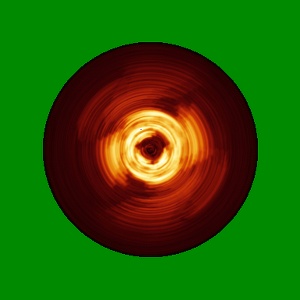

In vitro assembled 266/297 - 391 tau filaments with MgCl2 and NaCl (14b)

EMD-14044

Helical reconstruction

3.26 Å

Sample Organism: Homo sapiens

Sample: Tau

Fitted models: 7qkj

Deposition Authors: Lovestam S, Scheres SHW

Assembly of recombinant tau into filaments identical to those of Alzheimer's disease and chronic traumatic encephalopathy.

Lovestam S, Koh FA, van Knippenberg B , Kotecha A , Murzin AG, Goedert M , Scheres SHW

(2022) eLife , 11

PUBMED: 35244536

DOI: doi:10.7554/eLife.76494